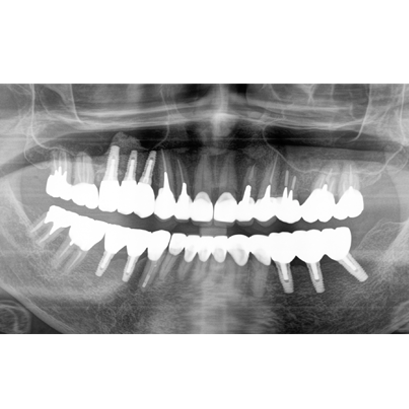

24.パノラマレントゲン

↑2024年6月26日

25.初診より18年経過(2024年6月26日)